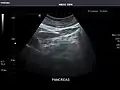

Pancreas -